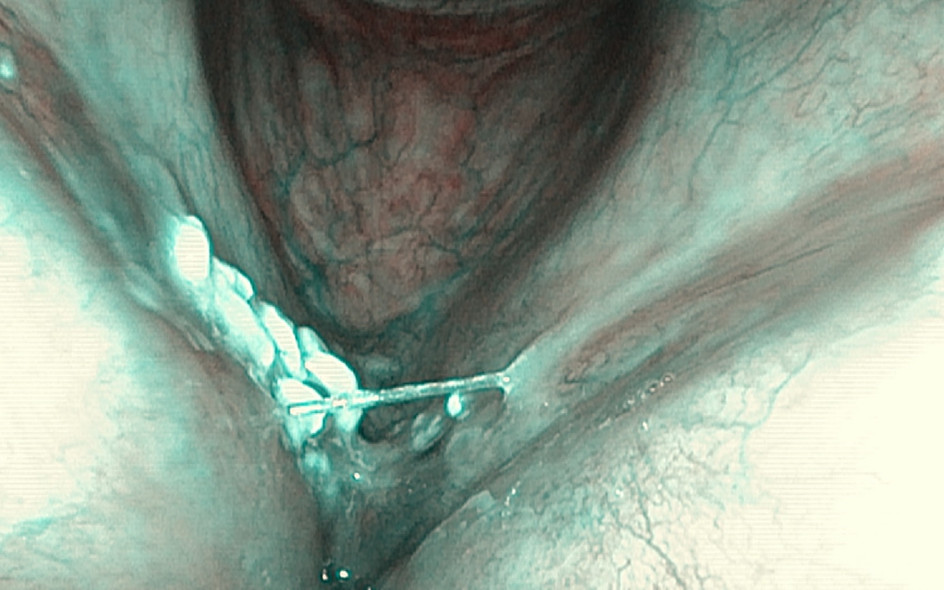

Patient No 1.

4x operations due to recurrent leucoplakia of the vocal folds

Chronic inflammation/biofilm

(CO2 laser)